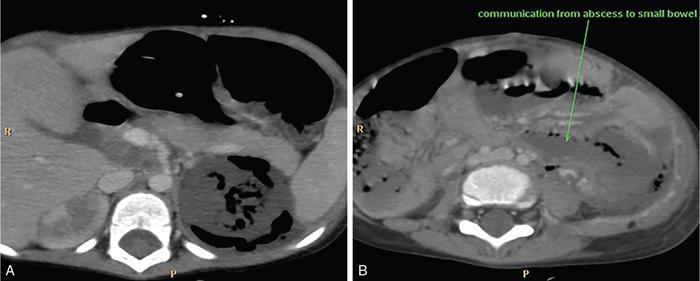

It is a rare necrotizing infection of kidneys with abnormal accumulation of air within parenchyma, pelvicalyceal system and in perinephric soft tissue. If not treated early, it can lead to morbid sepsis. Adult females are commonly affected. It tends to affect patients with uncontrolled diabetes, urinary tract obstruction, immunocompromised individuals, neoplasms or sloughing of papilla. Presenting complaints are fever, chills, flank pain, nausea and vomiting. Leucocytosis, raised white blood cell count, ESR, C-reactive protein, hyperglycaemia, acidosis, dehydration and electrolyte imbalance are prominent findings. Glucose fermenting bacteria such as E. coli (most common), Klebsiella, Pseudomonas and Proteus mirabilis are the causative organisms. Proteus, Aerobacter and Candida are additional causative organisms. Air is visualized as mottled lucencies within the renal fossa or crescentic collections of gas within the Gerota’s fascia. On grey scale imaging, there may be nonvisualization of the kidney due to air. Dirty echogenic foci with reverberation/ring-down artefacts representing gas (‘dirty shadowing’) in renal parenchyma, pelvicalyceal system and perinephric soft tissue are also seen. Renal enlargement may be seen. CTU is the most accurate and diagnostic modality. Kidneys appear enlarged and show destruction of renal parenchyma with accumulation of air in the parenchyma pelvicalyceal system and perinephric soft tissue (Fig. 10.12.2.2.1).